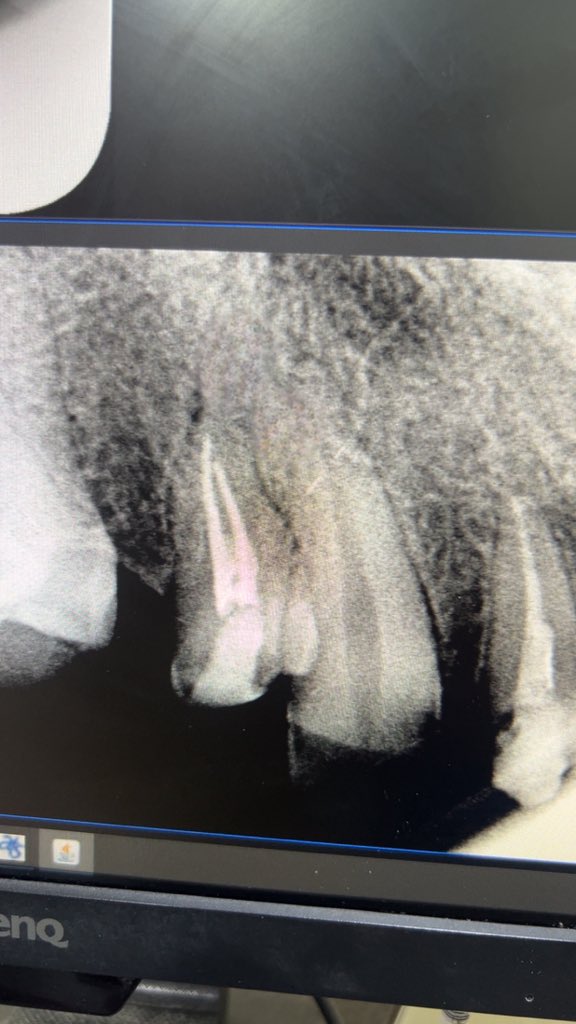

حالة جميلة لصباح اليوم 🙏🏻

Root Canal Treatment #34

Dx:SIP+SAP

Gingival overgrowth and deep caries in the distal wall, Rebuild the distal wall to achieve optimum isolation ✨

Next Step: Crown